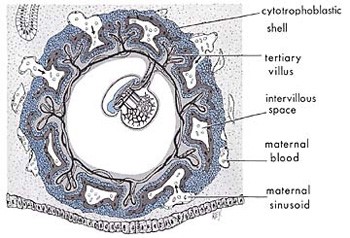

معنای دوم کلمه علقه «شیء معلق» است درست شبیه چیزی که در اشکال 2 و 3 میبینیم.

شکل 2: این نمودار تعلیق جنین در مرحله لقاح در رحم مادر را نشان میدهد.